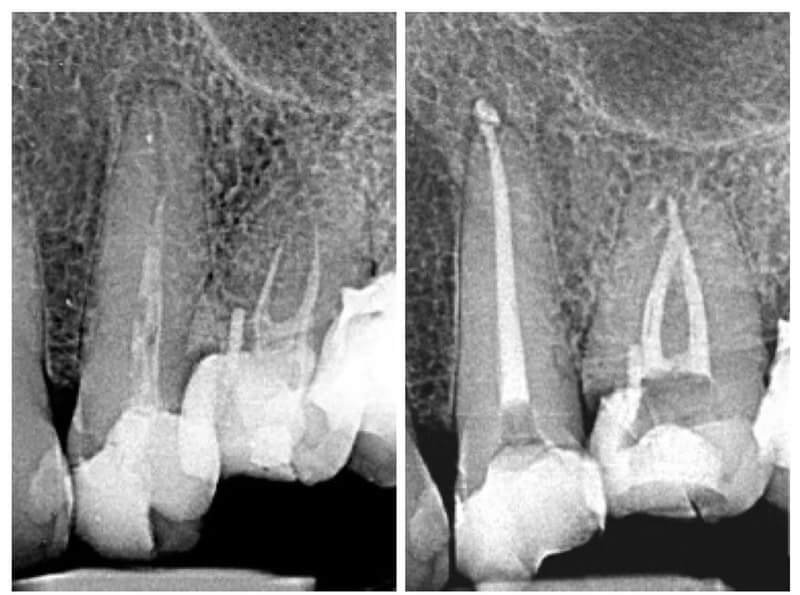

Endodonția este o ramură esențială a stomatologiei, axată pe diagnosticarea, prevenirea și tratamentul afecțiunilor pulpei dentare și a țesuturilor periapicale. Această specialitate joacă un rol crucial în salvarea dinților naturali, evitând extracțiile și menținând sănătatea orală pe termen lung. Prin tehnici avansate și echipamente de ultimă generație, endodonția asigură tratamente precise și eficiente, contribuind la redarea sănătății și funcționalității dinților într-un mod durabil și predictibil.

Utilizarea tehnicilor moderne asigură un tratament rapid, precis și confortabil pentru pacient.

Reconstituirea coronară cu materiale de calitate conferă rezistență pe termen lung.

Tratamentele corecte reduc riscul de infecții și complicații viitoare.